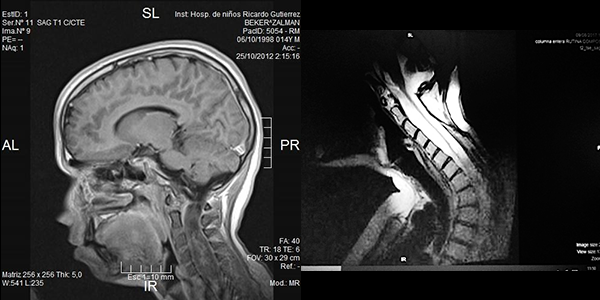

Es evidente que el límite entre el tejido medular y tumoral en las lesiones como los astrocitomas es indiscernible lo que dificulta la posibilidad de resección completa; en los tumores como los ependimomas esta diferencia es más franca y permite seguir un plano de disección seguro (Figuras 3, 4 y 5). Lo anterior condiciona nuestros resultados como han puntualizado diversos autores.5,8 El estado general previo a la cirugía requiere de una valoración juiciosa de las posibilidades de resección. Por ejemplo, el caso 12 (Figura 6) es una paciente portadora de Enfermedad de Von Hippel Lindau, Hemangioblastoma cervical biopsiado en otra institución del exterior del país, fijación de columna cervical y sindrome de Cushing por exceso de medicación corticoidea cuya cirugía debió suspenderse en dos oportunidades por la disminución de su capacidad ventilatoria. Con estos antecedentes y la delgada capa de tejido medular evidenciada intraoperatoriamente se optó por una resección subtotal. A los cuatro meses de la cirugía la paciente recuperó la marcha autónoma y demás parámetros clínicos.

Figura 3: Caso 10. Ependimoma cervical pre operatoria: Lesión sólida C3 y dilatación siringomiélica. Posoperatorio: resección completa, disminución de la cavidad. Restos hemáticos decantados.

Respecto del monitoreo intraoperatorio, la utilidad del registro de potenciales evocados, Onda D o Electromiografía dependerá no solo de la obtención de respuestas sino también del diálogo entre el cirujano y el neurofisiólogo,11-13 debido al fenómeno de falso negativo y positivo como se muestra en la Tabla 4. El cirujano recibe la información con retraso al evento y en ocasiones las maniobras de “reanimación” medular (irrigación con suero tibio, corticoides, etc.) no son concluyentes produciendo el abandono de una resección factible. La laminoplastía busca favorecer la restitución del alineamiento espinal, pero debe mantenerse un control, en particular en tumores de la unión cérvico dorsal, sobre el desarrollo o acentuación de escoliosis (Figura 3), en ocasiones presente al diagnóstico y que se acentúa en la evolución posoperatoria.13,16